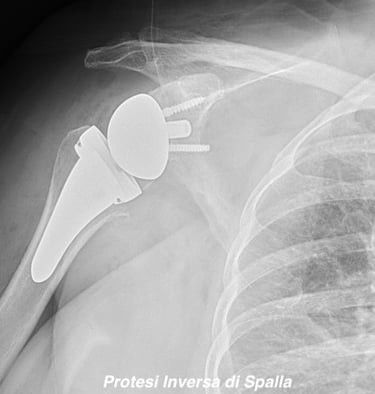

Chirurgia di Spalla e Gomito

Eseguo visite specialistiche, trattamenti conservativi e interventi specialistici sulla spalla e sul gomito, sia artroscopici sia a cielo aperto, per il trattamento delle principali patologie ortopediche e traumatiche di queste articolazioni.

Artrosi di spalla (Gleno-Omerale)